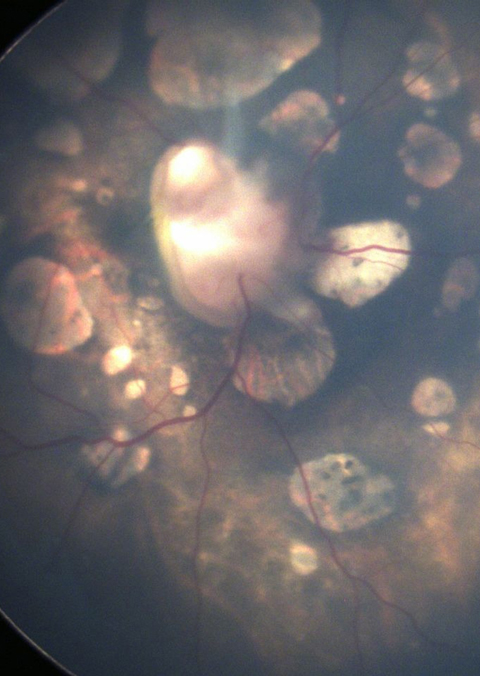

Choriretinal lacunae aid in the diagnosis of Aicardi syndrome